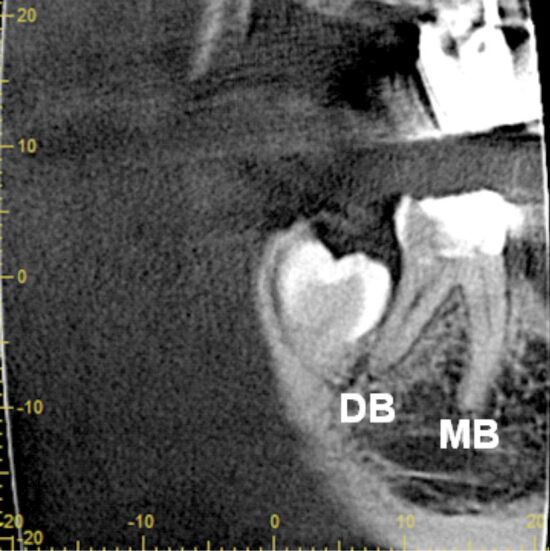

特别是在磨牙中,有时可能有异常的额外根管,个别病例中牙齿内部形态的复杂性有时与公认的分类规则不匹配,并突出了在牙髓治疗过程中错过解剖结构的风险。据我们所知,一个永久性下颌第二磨牙有五个独立的根,三个近中根和两个远端根,每个根都有一个根管,目前尚未报道。尽管治疗困难,但通过使用牙科手术显微镜和小视场的锥束计算机断层扫描(CBCT),可以成功地接近这颗牙齿。虽然CBCT不是一种常规的影像学检查,但在非典型牙齿解剖的情况下,旨在制定适当的诊断和治疗计划,成功的临床结果优于照射剂量。

Especially in molars that may have sometimes aberrant additional root canals, the complexity of tooth internal morphology in individual cases sometimes does not match to admitted classification rules and underlines the risk of missed anatomy during the endodontic management. To our knowledge, a permanent mandibular second molar with independent five roots, three mesial and two distal, each of them harboring a single canal, was not yet reported. Despite the treatment difficulties this tooth could be successfully approached by using dental operative microscope and cone-beam computed tomography (CBCT) with small field of view. Though CBCT is not a routine imagistic examination, in case of atypical tooth anatomy aiming to establish adequate diagnosis and treatment plan, the successful clinical outcome prevails over the irradiation dose.